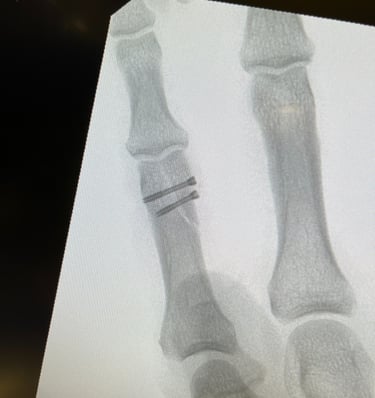

Polso e Mano

Mi occupo del trattamento delle principali patologie della mano e del polso, sia degenerative che traumatiche. Tratto condizioni frequenti come sindrome del tunnel carpale, dito a scatto, tendiniti e traumatologia della mano e del polso, con approccio conservativo o chirurgico mirato al recupero della funzionalità e alla riduzione del dolore.